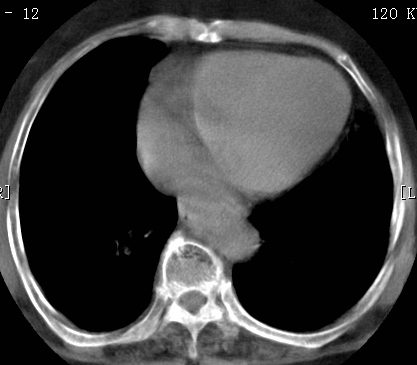

考虑1、周围型肺癌,2肺静脉畸形,前者可能大,建议增强检查。

考虑1、周围型肺癌,2肺静脉畸形,前者可能大,建议增强检查。支持!

不排除右肺下叶周围型肺癌可能。

中心型肺癌,纤支镜可帮助明确。